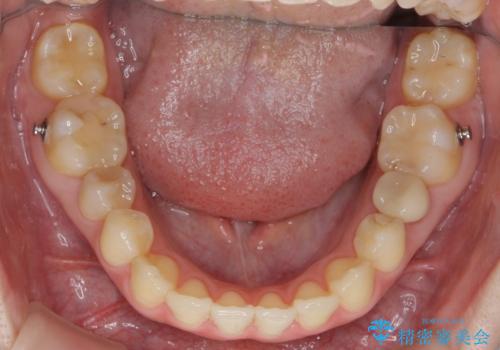

犬歯のねじれ 上の歯が引っ込んでいる

- 2年8ヶ月

- 前歯の並びを気にして来院。

インビザラインで、上の前歯をやすり掛けして並べました。

途中妊娠、出産を挟み、患者様がアライナーがつけられない時期もあって治療自体は延長しました。